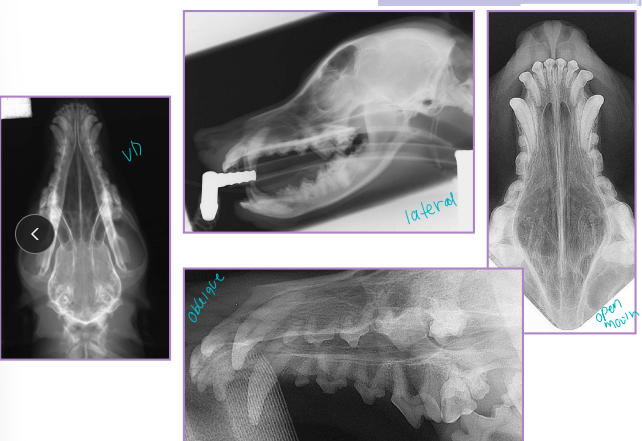

Fractures of the Mandible and Maxilla

Check occlusion!!

Considerations:

Body: bending forces, tension greatest at alveolar surface

Ramus: shear forces

Symphysis/Incisive region: rotational forces

Et: Trauma, severe dental disease, neoplasia

Mandibular: Dogs body and cats incisor region

Maxillary: Dogs alveolar region and cats midline palate separation

Dt: Rads, CT for surgical planning

Comp: Dental issues, malocclusion, facial deformity, oronasal fistula, palate defects, osteomyelitis, bone sequestration, delayed union/non-union

Treatment for Fractures of the Mandible and Maxilla

Keep teeth for stability & occlusion, strong fixation and tension at alveolar surface, pharyngostomy intubation

Non-surgical:

Tape muzzle: cheap, easy, unilateral stable fractures

not good for cats/brachycephalics

Symphyseal wiring: cats, cerclage wire between canines, 6-8w healed

Maxillomandibular bonding: bonds upper/lower canines, cats/brachycephalics

aspiration risk, slurry diet needed

Interdental splinting: acrylic/wire splinting, good for rostral, requires stable teeth

Surgical:

Interfragmentary wiring: good for linear, 2-piece fractures, requires exact reduction

not good for comminution/bone loss

Plates & screws: body/ramus, avoid tooth roots & mandibular canal, place ventrolaterally

ESF: strong, min invasive, high postop care, self-trauma risk